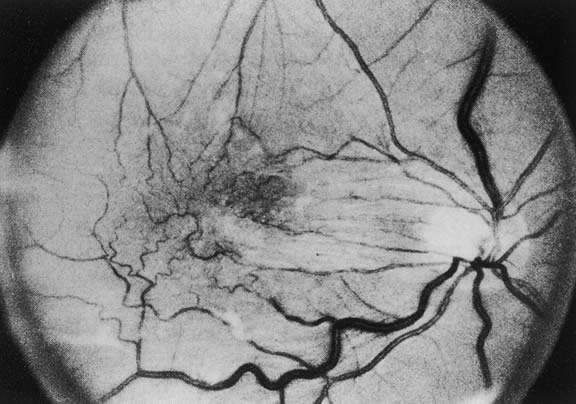

MACULAR EPIRETINAL MEMBRANES

Macular epiretinal membranes are a vitreoretinal condition characterized by cellular proliferation on the anterior surface of the ILM of the macula usually occurring after PVD. This proliferation may also occur as a result of inflammation, retinal vascular occlusion, retinal breaks, or detachment. However, there is commonly no associated ocular disease, and this proliferation is then classified as idiopathic. A number of descriptive terminologies have been applied to this condition, including preretinal macular fibrosis, surface wrinkling retinopathy, cellophane maculopathy, primary retinal folds, and macular pucker. Gass102 proposed a three-grade classification for these epiretinal membranes. Grade 0 is for translucent, shiny membranes without retinal distortion corresponding to cellophane maculopathy. Grade 1 is for membranes that have contracted or shrunk resulting in inner retinal irregular folds. Fine superficial radiating folds extending outward from the margins of the contracted membrane are often the most easily distinguished biomicroscopic evidence of an epiretinal membrane. The reduction in visual acuity from these epiretinal membranes is primarily a result of the distortion of the outer retinal layers and not a function of the thickness of opaqueness of the membrane (Fig. 21). Thicker, more opaque membranes that obscure underlying vessels and cause full-thickness retinal distortion are classified as grade 2 corresponding to macular pucker. Retinal edema, small retinal hemorrhages, cotton-wool spots and exudates may all be seen in conjunction with these more opaque membranes. Grade 2 membranes are also referred to as macular pucker (Fig. 22). In this chapter, we use the term macular epiretinal membranes, which is used to encompass the spectrum of this condition.

Fig. 21. Grade 1 epiretinal membrane.

Fig. 22. Grade 2 epiretinal membrane.

The incidence of idiopathic macular epiretinal membranes is approximately 3.5% at autopsy, and they are unilateral in 80% of cases.103 As noted previously, the clinical appearance of macular epiretinal membranes ranges from a transparent sheet with no effect on the retina to an opaque white tissue with obscuration of the underlying retina and full-thickness retinal distortion. The membrane's effect on vision can vary greatly. Patients can present with fine translucent epiretinal membranes that may remain stable for many years, resulting in only mild visual symptoms. Patients with full-thickness retinal folds secondary to macular pucker may complain of metamorphopsia or decreased vision resulting from macular edema or localized serous detachment of the retina. Epiretinal membranes can demonstrate areas of pigmentation within the membrane, possibly secondary to migration of RPE cells. This pigmentation is most commonly found in membranes seen following repair of a rhegmatogenous retinal detachment or following a retinal tear. These pigmentary cells may be liberated into the vitreous cavity through the retinal break. Idiopathic epiretinal membranes are rarely pigmented. A PVD is present in 80% to 95% of idiopathic macular epiretinal membranes and is, therefore, believed to be important in the pathogenesis of idiopathic epiretinal membranes. It is postulated that a PVD may disrupt the ILM, resulting in the migration of retinal glial or other cells through the ILM onto the retinal surface.104 These microbreaks in the ILM may allow astrocytes, glial cells, fibroblasts, and other contractile tissue to migrate along the retinal surface, thus, forming an epiretinal membrane that may undergo contraction. Histologically, idiopathic macular epiretinal membranes consist primarily of fibrous astrocytes derived from retinal glial and RPE cells. Other cells, such as fibrocytes and myofibrocytes, are identified in 8% to 20% of cases.10 Conditions such as a retinal detachment and/or retinal tear may directly liberate RPE cells, which can proliferate on the retinal surface, into the vitreous cavity. However, because there is no full-thickness retinal disruption present by definition in idiopathic epiretinal membranes, it is unclear how RPE cells enter the preretinal space. The retinal glia can stimulate proliferation of RPE cells.105 One possible scenario for idiopathic epiretinal membranes is (1) PVD leading to disruption of the ILM, (2) migration of retinal glia through the ILM, and (3) proliferation of retinal glia resulting in stimulation of RPE cell migration through the retina and proliferation on the retina. In addition, PVDs can often result in vitreous hemorrhage from disruption of retinal blood vessels. It may be that this vitreous hemorrhage liberates cells from within the retina that may stimulate proliferation on the macular surface.